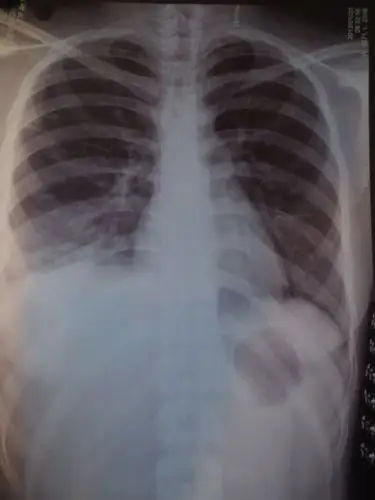

今天拍了片后说 是肺炎 但是我不咳嗽 就是有点流鼻涕 有时候呼吸超级